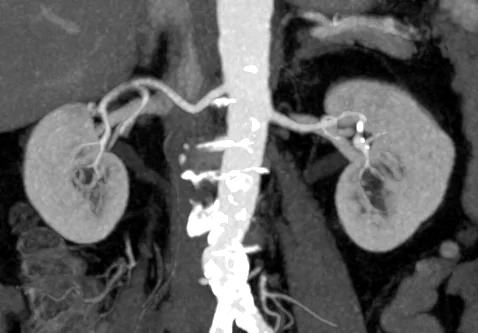

Применение контрастного агента зачастую необходимо в случае проведения первичной дифференциальной диагностики новообразований и уточнения детальной локализации, мониторинге результатов терапевтических/хирургических лечений онкологических заболеваний, а также для оценки сосудистого русла и его физических характеристик. Стоит отметить, что в диагностике сосудистых патологий, таких как мальформации, стенозы и атеросклеротические бляшки данный метод диагностики является “золотым стандартом”.

• Сосудистая система (мальформации, стенозы, повреждения сосудов, атеросклеротические бляшки и кальцификаты). Ранняя диагностика факторов риска развития инсульта;